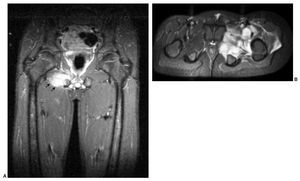

La RM contribuye al diagnóstico diferencial de la piomiositis con otras entidades como la artritis séptica, la osteomielitis, la tromboflebitis y el tumor. Asimismo, la administración de gadolinio identifica la presencia de abscesos, siendo de gran utilidad en el caso de que requieran drenaje percutáneo. Las áreas de piomiositis se manifiestan en una fase inicial como zonas heterogéneas y con elevada señal en las secuencias potenciadas en T2 y STIR. En fases tardías, los abscesos se presentan como áreas de baja señal en T1 y alta señal en T2, que realzan de manera periférica tras la administración de gadolinio (fig. 5), hallazgos que coinciden con la serie presentada por Soler et al21. Cambios en la señal del hueso se vieron en 7 de nuestros casos, mientras que una captación gammagráfica positiva sólo se apreció en 4 casos; esto indica que la RM es altamente sensible para identificar la patología ósea subyacente, aunque es difícil diferenciar si estos cambios en la señal del hueso se deben a la presencia real de osteomielitis o a edema reactivo. En estos casos el citrato de galio-67 y los leucocitos marcados con 111In o 99mTc pueden aumentar la sensibilidad y especificidad de la prueba radioisótopica22,23. El citrato de galio administrado por vía intravenosa se fija a la transferrina y se une a la lactoferrina de los leucocitos, e incluso a las propias bacterias, y se acumula en mayor cantidad en los focos inflamatorios y sépticos.

Fig. 5. (A) Fase purulenta. FSE T1 que muestra una zona de baja señal en el obturador externo derecho, sugestiva de pequeño absceso. (B) Fase purulenta; la misma imagen en secuencia STIR que muestra la hiperseñal del absceso. (C) Absceso del músculo psoasilíaco. Resonancia magnética en plano coronal FSE T1 tras la administración de gadolinio intravenoso, que muestra múltiples imágenes hipointensas con realce periférico sugestivas de abscesos.